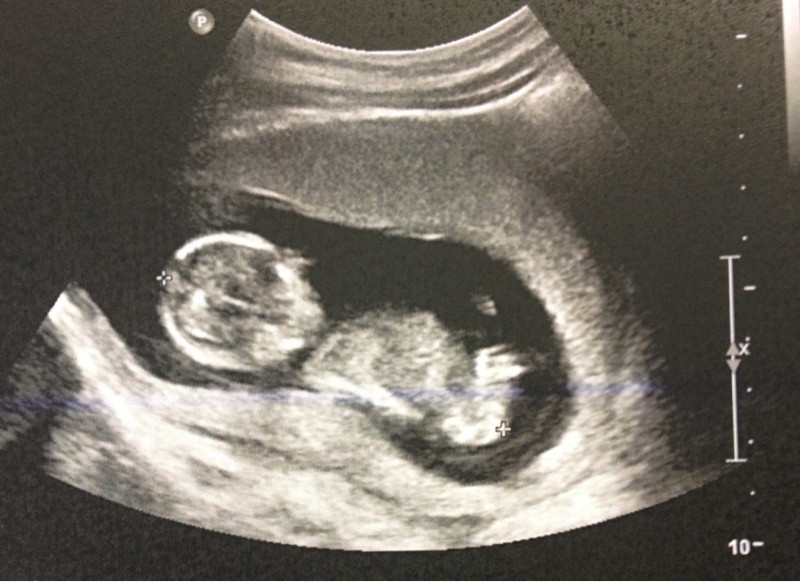

bébé pour l'été 2014 ;)

Voila

Dis moi ce que tu en penses ( j'ai que sa)

lol je vien de ressortir les echo de Nohlan pour voir comment ca fesai mais la honnetement je ne vois rien... a nohlan jai vraiment vu le kiki tout de suite (le gyneco l'a meme pris en photo lol) et a ma derniere echo on a vu egalement un kiki et ce qui va avec lol donc la je ne serai pas d'une bonne aide desole ma poulette

cest vrai que cest pas super comme photo mais apres niveau qualité ça va encore, pour bien voir y a pas mieux que la 3D mais bon financièrement faut suivre aussi...